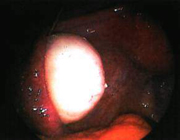

Исследователи из Лувэнского университета в Брюсселе (Бельгия) объявили о проведении успешной трансплантации яичников уже второй женщине. Это 28-летняя пациентка, яичники которой были удалены в 1999 году, до прохождения лучевой терапии серповидноклеточной анемии, которая сделала женщину бесплодной. После трансплантации у женщины возобновились месячные.

Полоски яичниковой ткани были извлечены у этой женщины до прохождения лучевой терапии. Они были разрезаны на кусочки и заморожены в жидком азоте. В августе 2004 года часть ткани была разморожена и трансплантирована в не функционирующие яичники женщины, и в январе 2005 года у нее возобновились месячные, что свидетельствует об успешной трансплантации ткани.

В сентябре прошлого года родился первый ребенок у женщины, которой была трансплантирована ткань яичников, - 32-летней Уарды Туйра. В это время были некоторые сомнения относительно того, являлось ли восстановление менструального цикла г-жи Туйра, а значит, ее фертильность, результатом процедуры трансплантации или естественным возвратом яичников к функциональному состоянию.

Профессор Жак Доннэ, глава группы бельгийских исследователей, представил результаты этого нового исследования на ежегодной конференции Британского Общества по репродукции человека и эмбриологии в Лондоне. Впервые о результатах этого исследования было сообщено в Вене, на 12-м международном конгрессе по репродукции человека. По словам профессора Доннэ, женщина еще не забеременела, но месячные у нее возобновились, и были налицо все признаки возврата репродуктивной функции.